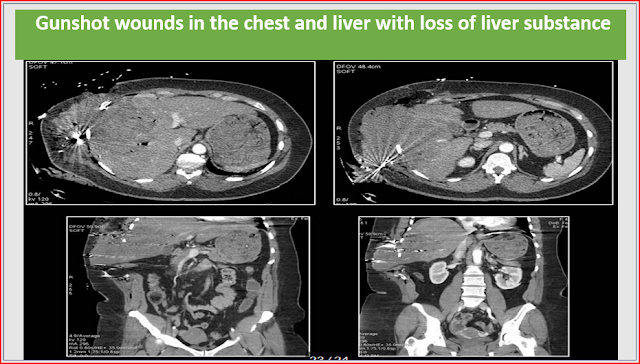

Traumatic